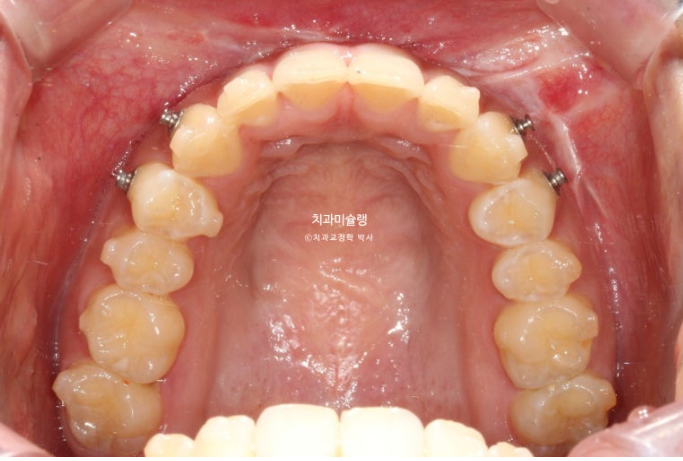

중심선은 정확히 맞으며

어금니 교합은 물샐틈 없는 1급 교합관계를 보입니다.

이제 교합 전후비교 보겠습니다.

25.02~25.10